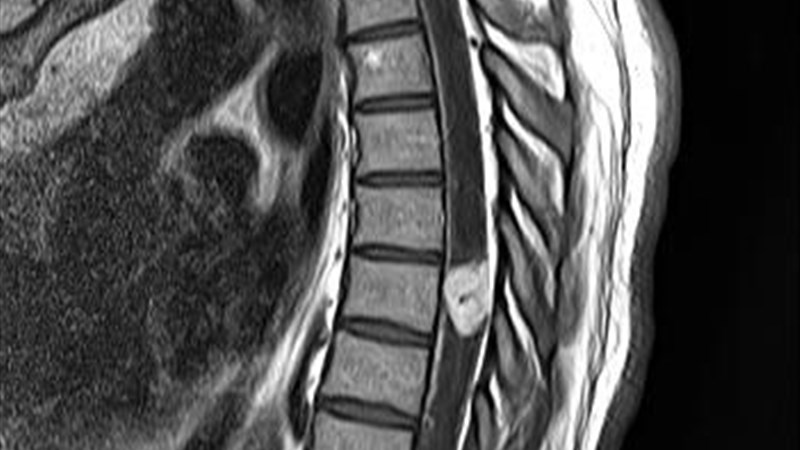

Отек спинного мозга что это

Отек спинного мозга что это 111 фото